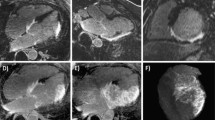

Image data acquisition was successfully completed in 32 out of 33 animals (97%) and in all 6 animals (100%) undergoing repeat CMR examinations. Heart rate ranged from 270 to 310 beats per minute (bpm), one CMR examination suffered from ECG-related triggering problems and could not be finalized. All 32 completed CMR examinations were of diagnostic image quality and constituted the final study population for analysis (for a representative imaging example see Figure 4 and Additional file 1).

Comparison of cine and late enhancement imaging (identical slice geometry). Representative example showing an end-diastolic cine short-axis frame (A) and the corresponding late enhancement image (B). White arrows indicate the akinetic (A) and infarcted region (B); see also movie 1 (see additional file 1).